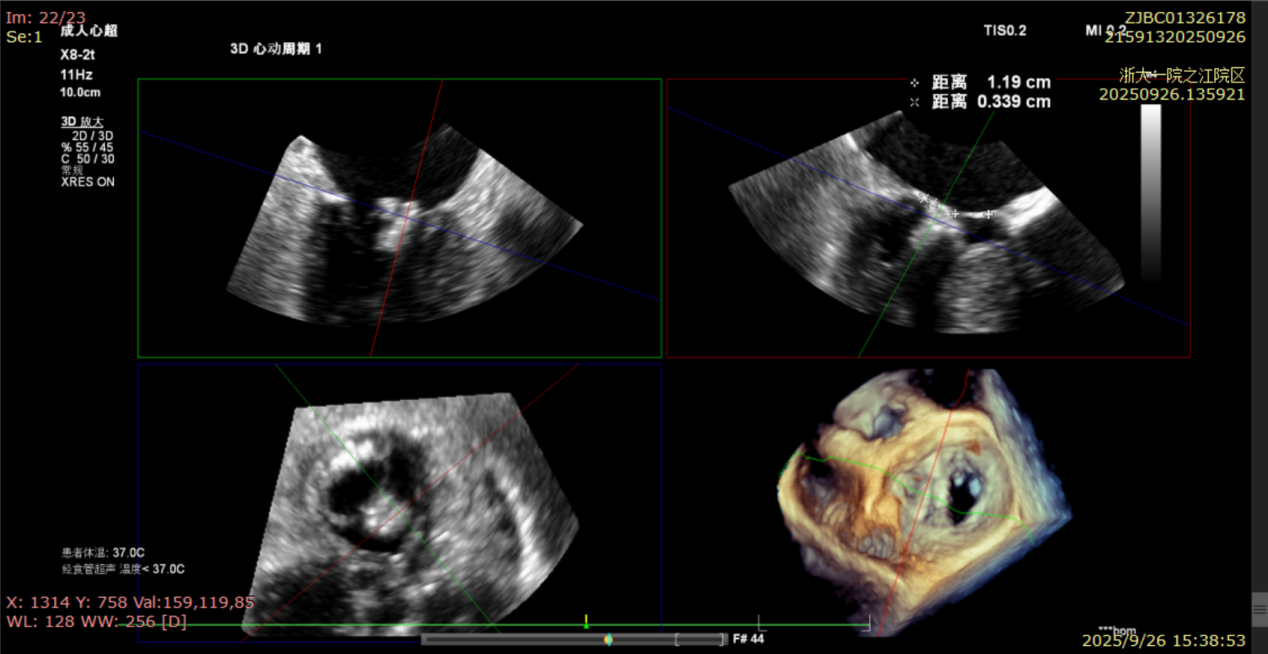

术后复查超声心动图显示:二尖瓣轻度返流,三尖瓣中度返流,二尖瓣可见金属夹回声,启闭正常;各心室大小正常,升主动脉不宽,主瓣回声增强,启闭良好;二尖瓣舒张期峰值流速1.4 m/s,功能面积2.1 cm²,跨瓣平均压差约4 mmHg。

术后心功能改善明显:LVdD 46mm,FS 33%,LA 45mm,LVDs 31mm,LVEF 62%。